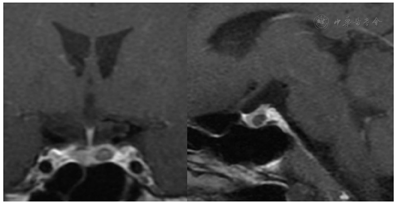

入院后查血清总皮质醇节律,8:00为37.8 μg/dL,0:00为36.57 μg/dL,24 h尿游离皮质醇(24hUFC)688.0 μg。考虑血皮质醇节律消失,24hUFC明显升高。过夜小剂量地塞米松抑制试验:服药后血皮质醇(8:00)34.1 μg/dL,考虑血皮质醇不被抑制,支持库欣综合征。血浆促肾上腺皮质激素(ACTH)8:00为122.0 pg/mL,符合ACTH依赖性库欣综合征。经典大剂量地塞米松抑制试验:对照日24hUFC 398.2 μg,血皮质醇37.4 μg/dL;服药后24hUFC 76.7 μg(抑制率80.7%),血皮质醇27.8 μg/dL(抑制率25.6%)。垂体动态+增强MRI:垂体左翼稍低强化灶(6.4 mm×4.7 mm×6.0 mm),考虑垂体微腺瘤可能(图1)。外周去氨加压素(DDAVP)兴奋试验结果见表1,用药后血皮质醇峰值达基线1.30倍,血ACTH达基线5.59倍。双侧岩下窦静脉取血(BIPSS)及DDAVP兴奋试验结果见表2,基线岩下窦(IPS)∶外周(P)最大值为1.385,刺激后IPS∶P最大值为1.702。

患者青年男性,慢性病程,有典型库欣综合征症状、体征,血皮质醇昼夜节律消失,过夜小剂量地塞米松抑制试验血皮质醇、24hUFC均不被抑制,ACTH>20 pg/mL,支持ACTH依赖性库欣综合征诊断。垂体动态增强MRI提示垂体左翼微腺瘤(6.4 mm×4.7 mm×6.0 mm)可能。完善BIPSS及DDAVP兴奋试验:基线IPS∶P为1.385,刺激后IPS∶P为1.702,均未达到上述BIPSS诊断库欣病的切点。

本例患者考虑为BIPSS假阴性的库欣病。患者垂体占位位于鞍内,岩下窦取血术中可见置管满意(图2),不考虑静脉结构或肿瘤位置变异。患者BIPSS基线ACTH水平在左、右岩下无明显差异,考虑BIPSS假阴性原因可能与肿瘤ACTH分泌无取血分侧差异相关。患者入院时、行BIPSS试验及外周DDAVP兴奋试验时的ACTH水平差异较大,故也有因肿瘤分泌ACTH波动导致的BIPSS假阴性的可能。